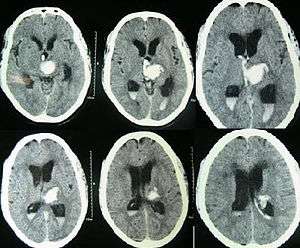

Intraparenchymal hemorrhage can be recognized on CT scans because blood appears brighter than other tissue and is separated from the inner table of the skull by brain tissue. The tissue surrounding a bleed is often less dense than the rest of the brain because of edema, and therefore shows up darker on the CT scan.[14]